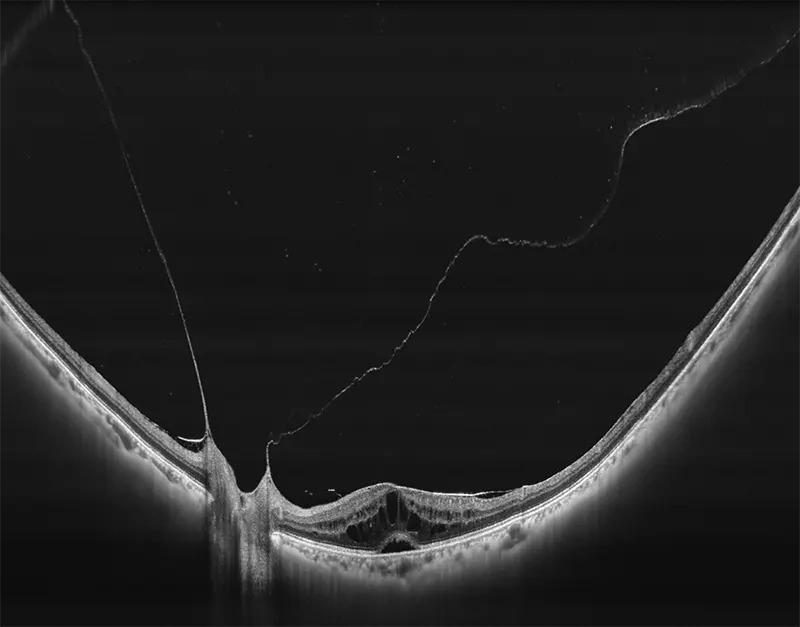

BMizar (BM-400K) es el OCT más potente de la industria con una fuente de barrido de 400 kHz. Su excepcional diseño óptico eleva la experiencia de la Angiografía OCT a un nivel sin precedentes. Con imágenes de alta definición de la retina, la coroides y el segmento anterior, cubre sin esfuerzo un área increíblemente grande en un solo escaneo (logrando un OCTA de 24 mm de ancho en solo 7-15 segundos).

Galería OCTs del TowardPi BMizar